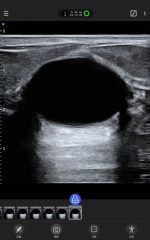

Galería de demostración

|